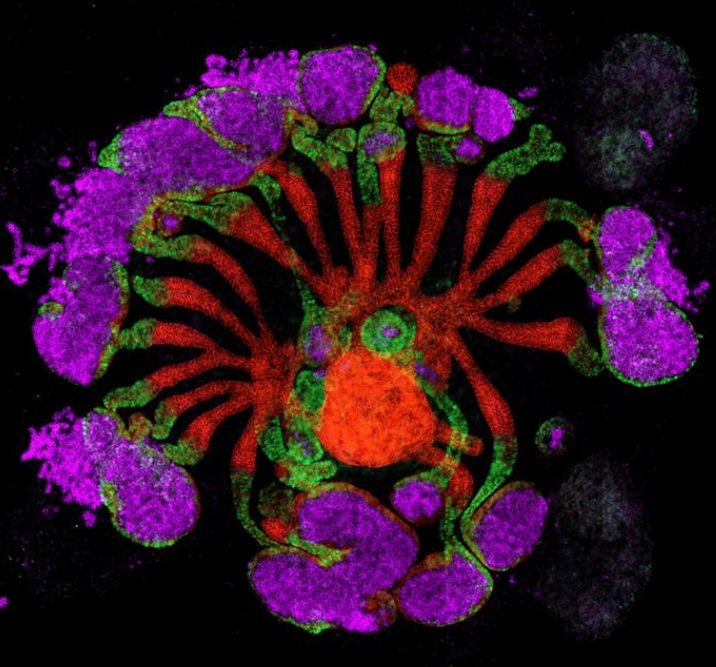

科學(xué)家創(chuàng)建出新型“組合體”腎臟組織